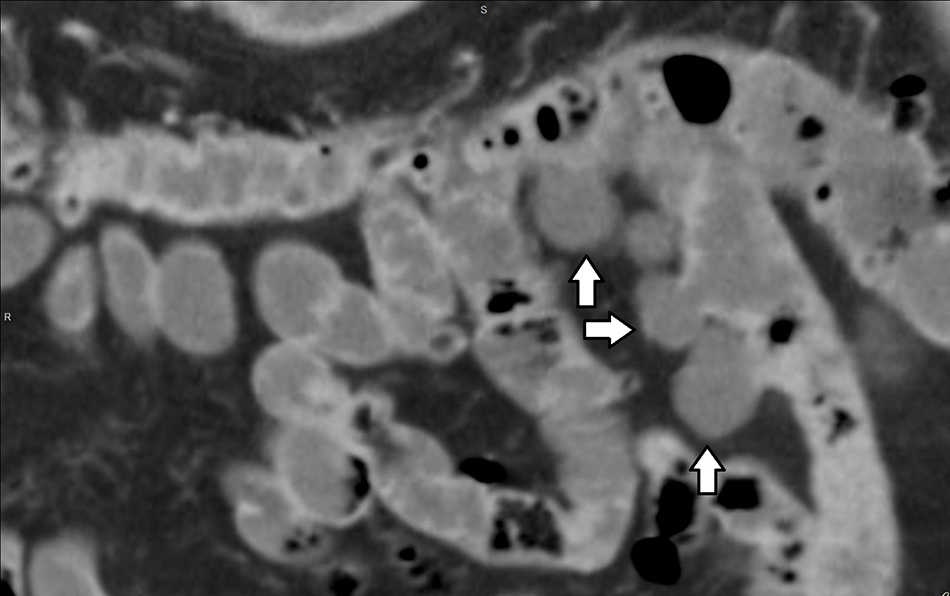

Diverticulitis y perforación (5%): se visualiza engrosamiento parietal y deformación de los contornos del divertículo complicado, con aumento de la densidad de los planos grasos adyacentes y formaciones ganglionares reactivas asociadas, generalmente en rango no adenomegálico. La TCMD descarta o confirma la existencia de colecciones abscedadas o de neumoperitoneo2 (figs. 2–5).

Obstrucción intestinal (3%): se observa obstrucción secundaria al proceso inflamatorio peridiverticular, con un área con cambio de calibre en el punto de partida del divertículo complicado. En el divertículo de Meckel, esta complicación ocurre en el 40% de los casos y se produce por una banda mesodiverticular, un vólvulo del divertículo, un mecanismo de invaginación (fig. 6) o por la extensión a un saco herniario8.